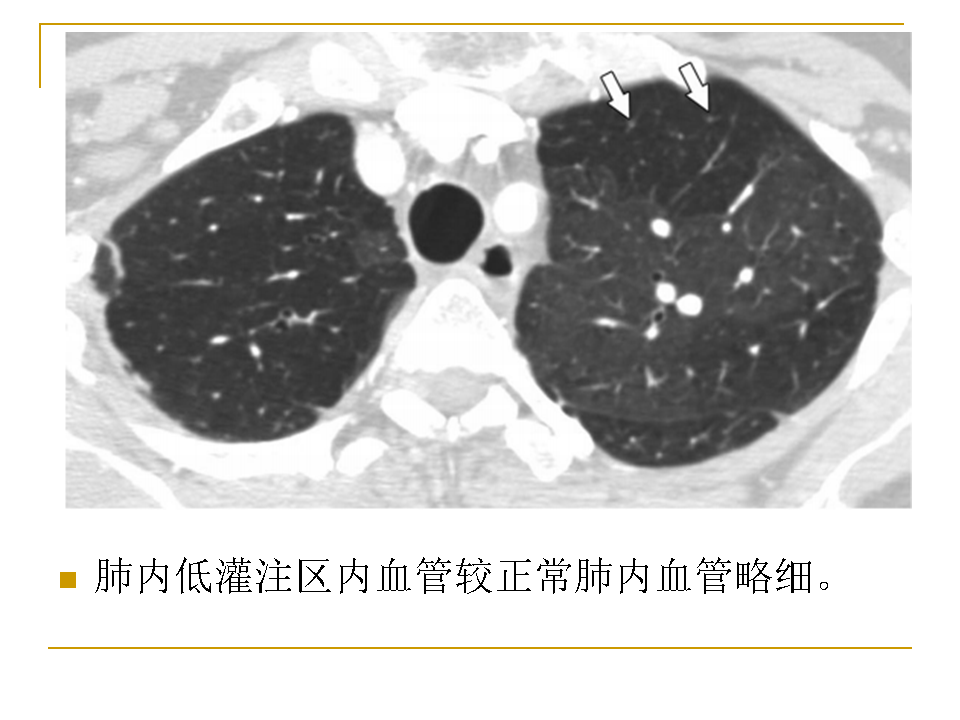

【RadioGraphics】肺动脉栓塞CTA